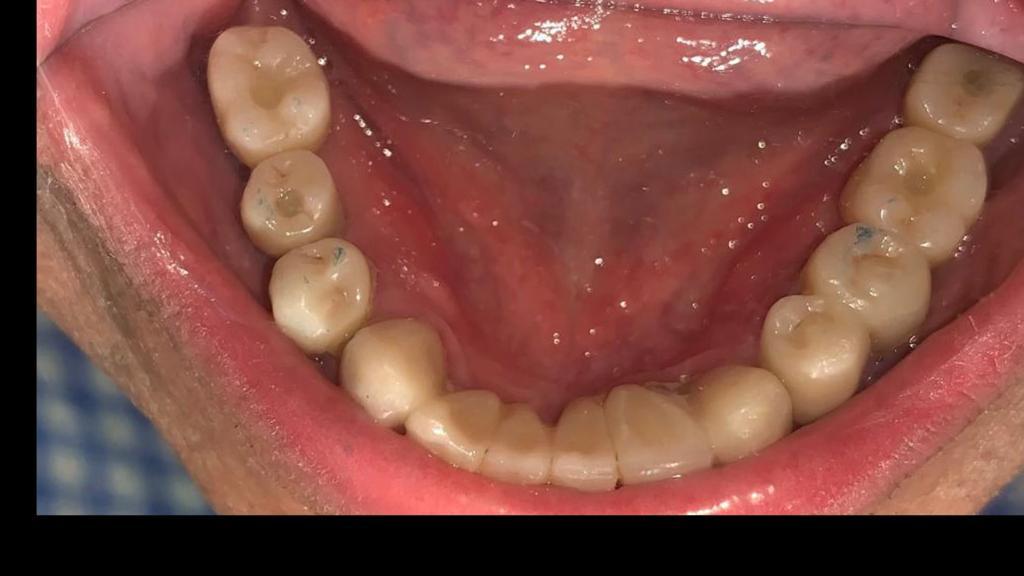

Fase 2: Preparación para implantes dentales

Fase 2

Etapa final con Coronas e Implantes dentales

Etapa de preparación y colocación de implantes dentales como base para la futura restauración protésica.